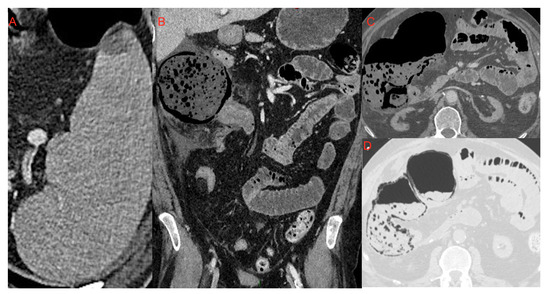

Figure 12. Small area of splenic infarction (A); infarction of the cecum and right colon (BD): It is possible to notice the marked dilatation of the ascending colon, with parietal pneumatosis and hydro-aerial levels. It was associated with abdominal effusion in right subhepatic space and paracolic gutter which extended to the pelvic cavity.

As described by Bhayana et al. [48] and Goldberg-Stein et al. [46] (reported also by Tirumani et al. [54] and Lui et al. [55]) the pathogenetic mechanism underlying intestinal infarcts in critical COVID-19 patients might be the thrombotic diathesis due to the inflammatory response to the infection. On CT examination we can see mesenteric arterial or venous filling defects, the “paper sheet wall” sign or the “target” sign with thickened wall, constituted by hyperdense mucosa and hypodense submucosa. In the more advanced stages this condition evolves with findings of hydro-aerial levels, and parietal and portomesenteric pneumatosis (Figure 12). Tirumani et al. [54] observed the frequency of intestinal infarction in 1/72 COVID-19 patients investigated with CT examination (1.3%).